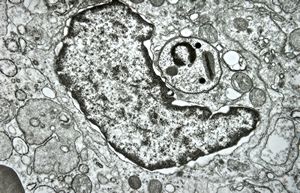

M, 11y. | mycosis fungoides v.s. - cerebriform nucleus of Sézary cell

F, 57y. | mycosis fungoides … cerebriform nucleus of Sézary cell

F, 37y. | mycosis fungoides … cerebriform nucleus of Sézary cell

M, 70y. | mycosis fungoides - Sézary cell

M, 70y. | mycosis fungoides - Sézary cell